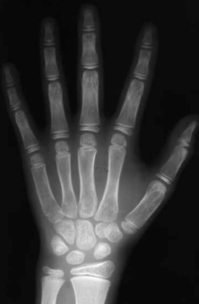

所以,家长应定期带孩子进行骨龄检测,以了解孩子的生长发育状况,及时采取干预措施。

就是给娃的左手拍个X射线片

测骨龄能反映儿童骨骼发育成熟程度,骨龄与年龄的关系密切,正常情况下应保持一致或相差不超过一岁。